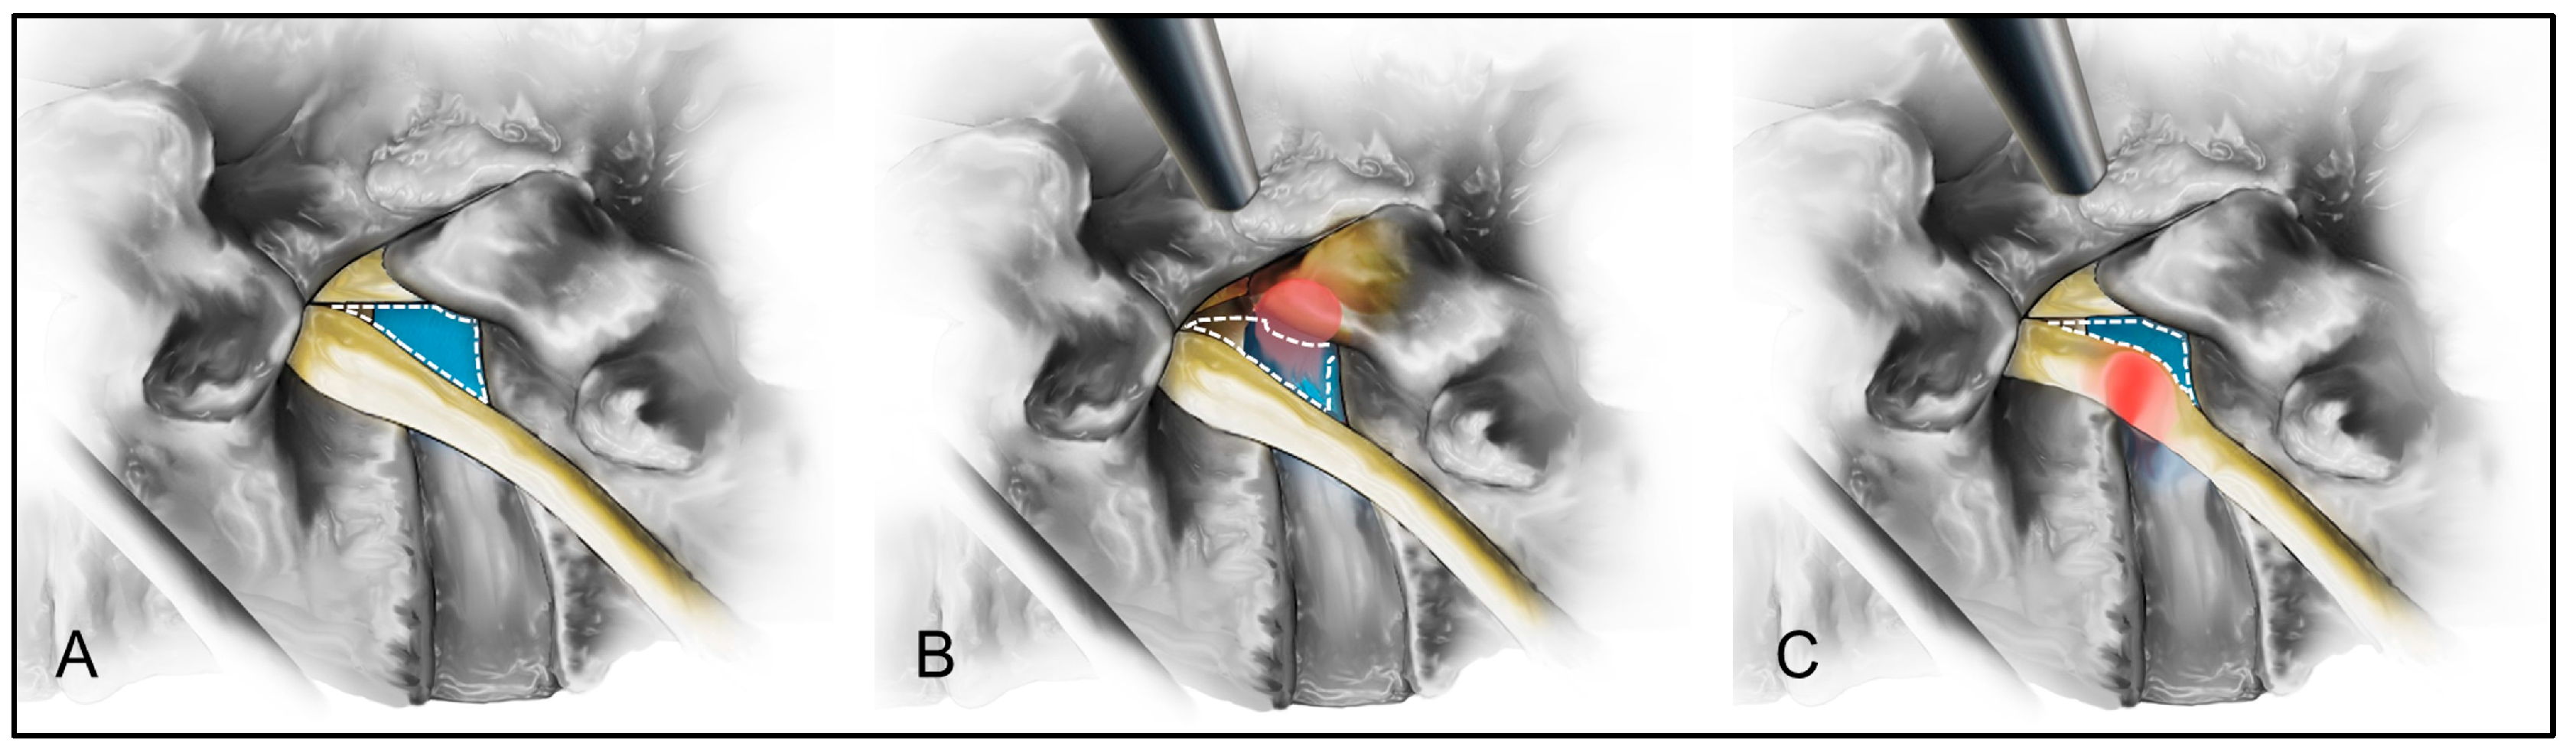

In TELD for extraforaminal LDH, patients experienced greater access pain, longer operative times, and longer hospital stays than those with foraminal LDH. A narrower safe working zone during the transforaminal endoscopic approach increases the likelihood of exiting nerve root irritation and pain [20,21,22]. In the present study, disc herniation within the extraforaminal zone may have further reduced the safe working zone during the transforaminal approach, thereby prominently exposing the exiting nerve root along the access pathway. This increased exposure likely exacerbated access pain, which, in turn, contributed to prolonged operative times and hospital stays (Figure 4). Therefore, particular attention should be paid to the strategies that minimize nerve root irritation and access pain while performing TELD for extraforaminal LDH.

Figure 4.

Schematic comparison of the safety working zones for the transforaminal approach in foraminal and extraforaminal lumbar disc herniation (LDH). The safety working zone (blue) in a standard lumbar disc is illustrated (A). For the foraminal LDH (red), the safety working zone (blue) may be narrowed but remain preserved for the transforaminal approach (B). In contrast, extraforaminal LDH (red) significantly narrows the safety working zone (blue), increasing irritation of the exiting nerve root and more significant access pain during the transforaminal approach (C).